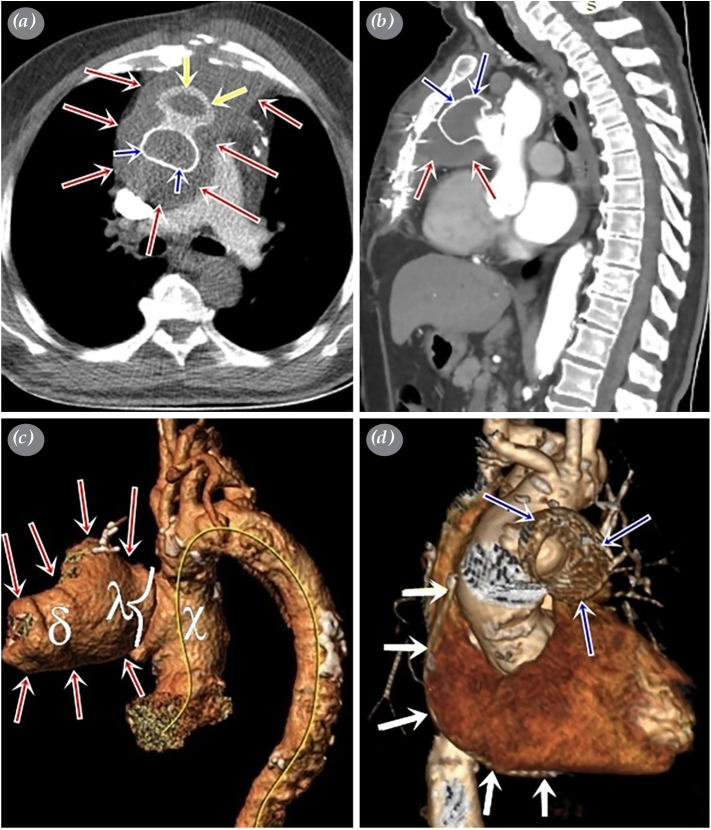

主动脉假性动脉瘤是一种罕见但严重的疾病,可导致危及生命的并发症。它通常是由以前的心脏手术、创伤或感染引起的。由于初级手术干预时血管破裂的可能性很高,在符合条件的病例中,血管内闭合可作为标准护理。在这篇文章中,我们提出了一个巨大的假性动脉瘤与宽颈,可以安全地使用房间隔封堵器关闭。

An aortic pseudoaneurysm is a rare, but serious condition which can result in life-threatening complications. It is usually caused by previous cardiac surgery, trauma, or infection. Due to the high likelihood of rupture with primary surgical intervention, endovascular closure may be performed as the standard of care in eligible cases. In this article, we present a case of a huge aortic pseudoaneurysm with a wide neck which could safely be closed using an atrial septal occluder.